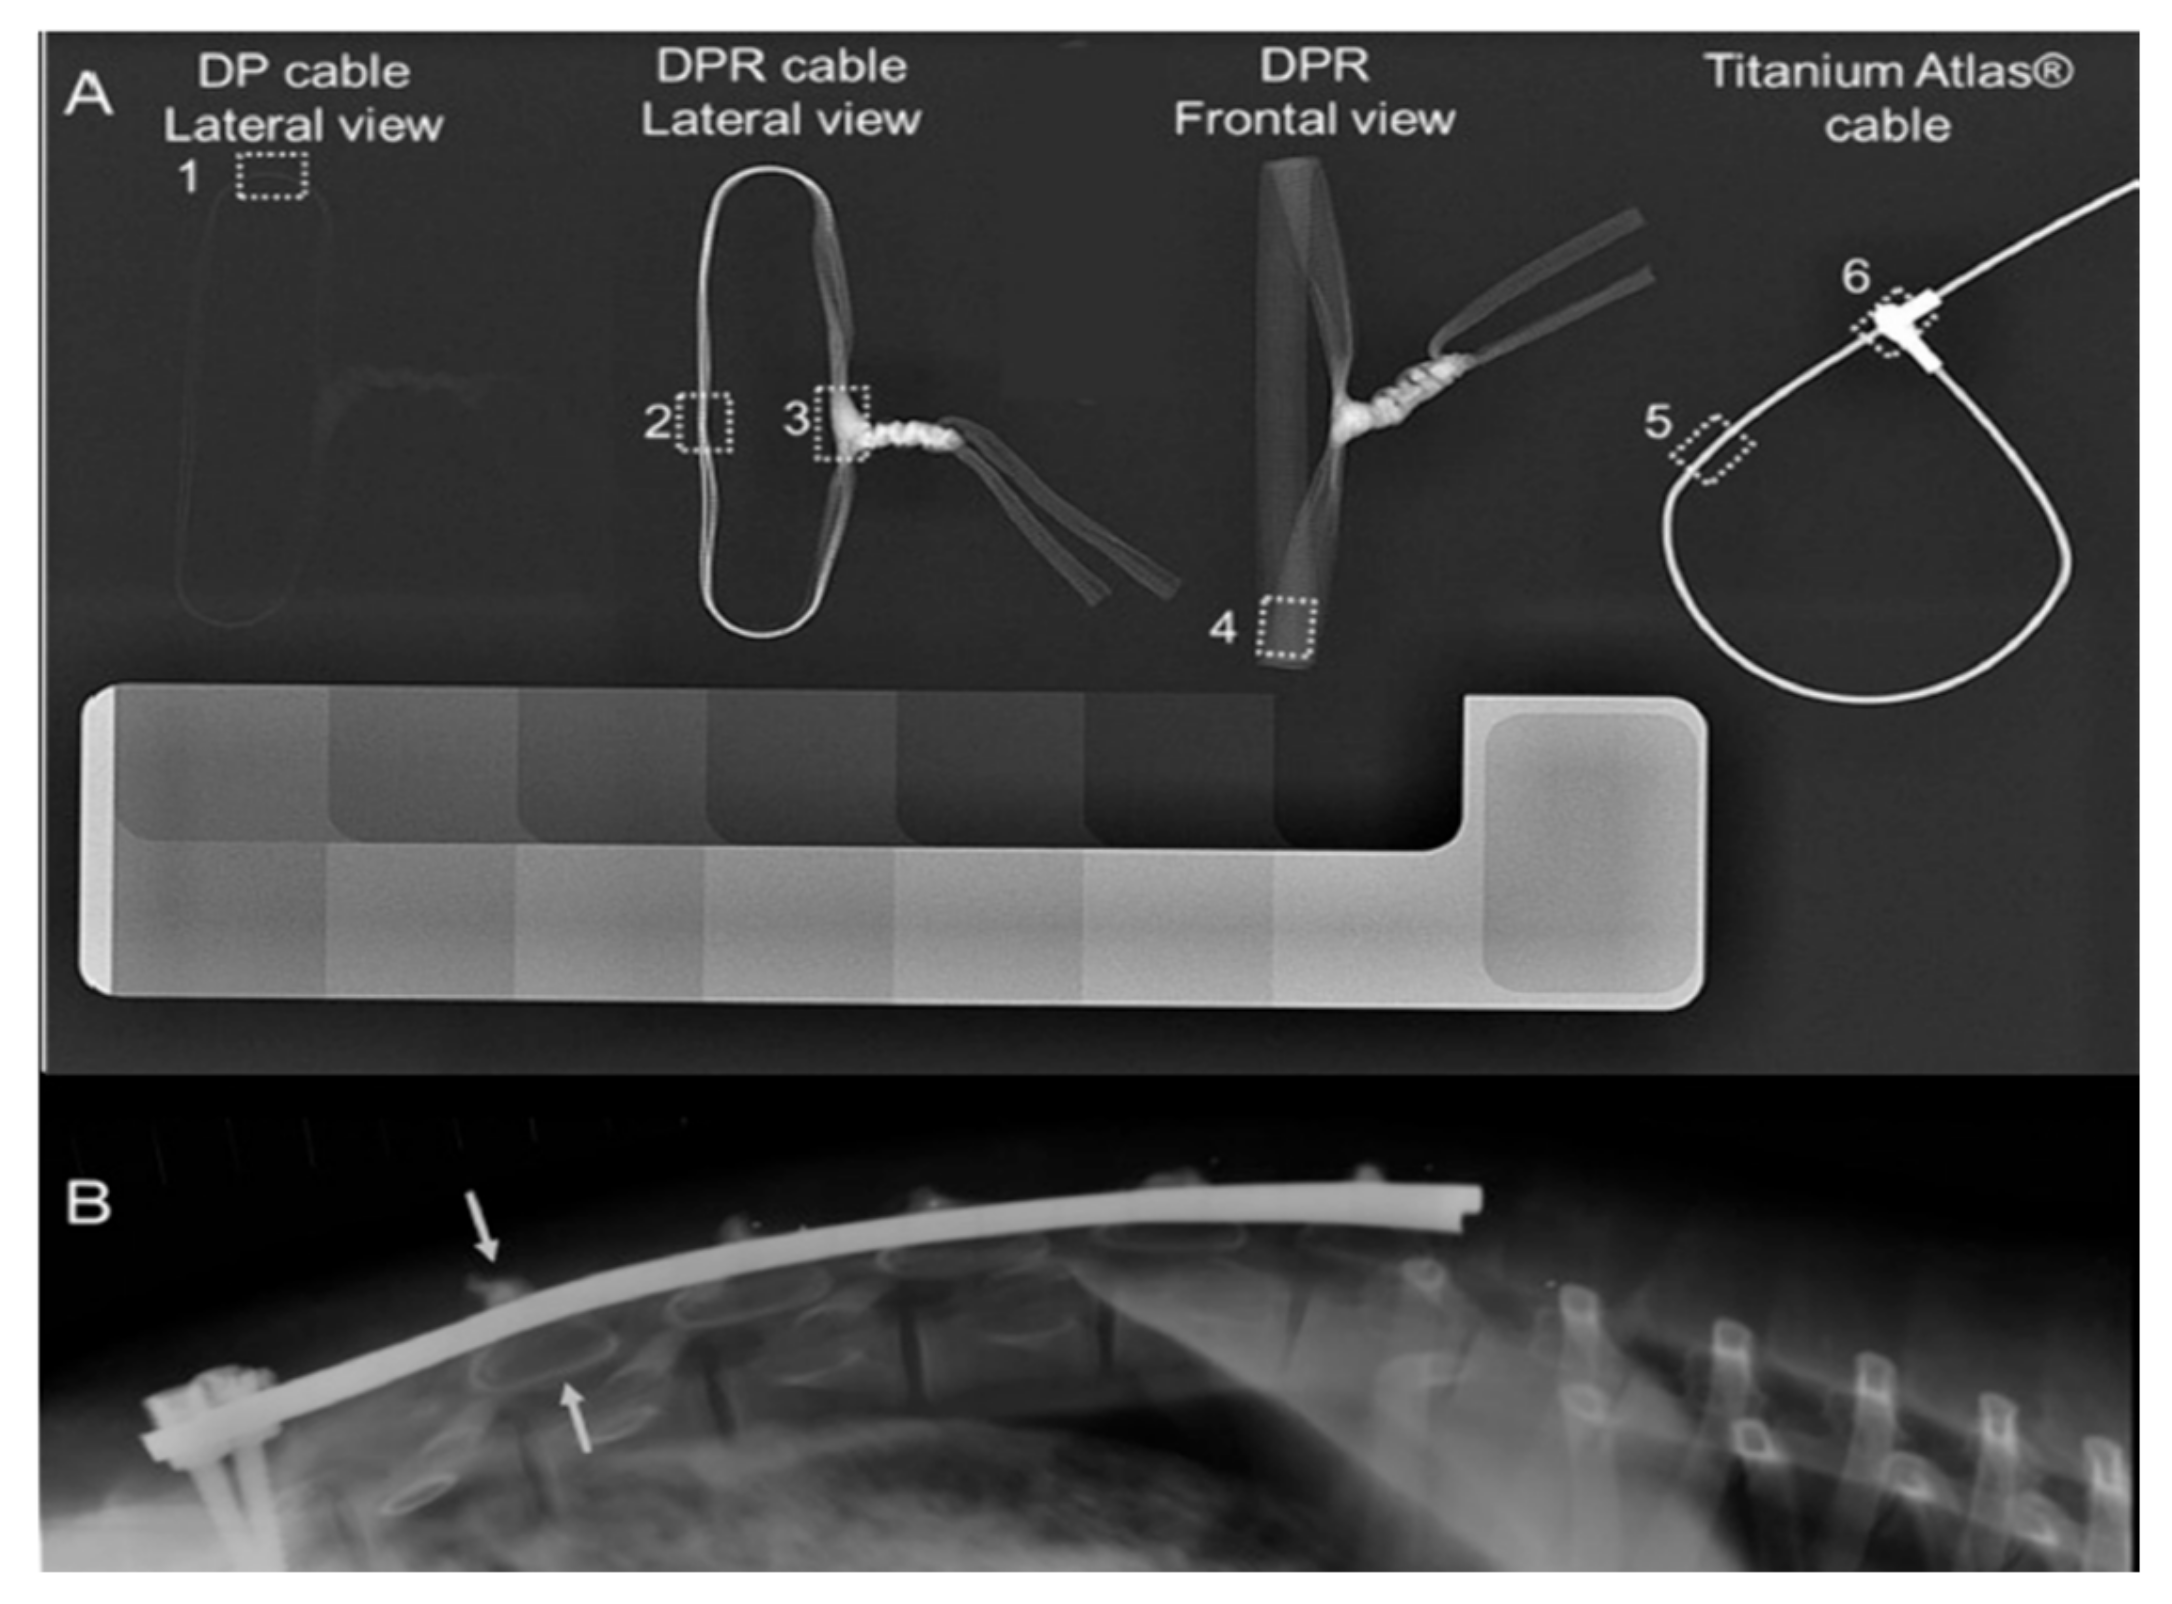

- Roth, A.K.; Karlien Boon-Ceelen; Smelt, H.; Bert van Rietbergen; Willems, P.; Rhijn, van; Arts, J.J. Radiopaque UHMWPE Sublaminar Cables for Spinal Deformity Correction: Preclinical Mechanical and Radiopacifier Leaching Assessment. Journal of Biomedical Materials Research Part B 2017, 106 (2), 771–779. [CrossRef]

- Bogie, R.; Roth, A.K.; Faber, S.; Jong; T. Welting; Willems, P.; Arts, J.J.; L.W. van Rhijn. Novel Radiopaque Ultrahigh Molecular Weight Polyethylene Sublaminar Wires in a Growth-Guidance System for the Treatment of Early-Onset Scoliosis. Spine 2014, 39 (25), E1503–E1509. [CrossRef]

| Bismuth oxide Bi2O3 | Blended into fiber | UHMWPE | Sublaminar cables | 20 wt % | Decreased tensile strength, limited leaching below toxic levels | NO | No adverse effects | [105] [106] |